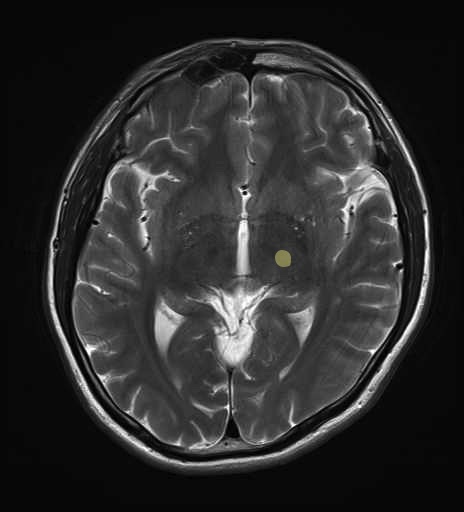

運動系 錐体路系に色を付けました。

■皮質脊髄路(いわゆる錐体路):一次運動野から脊髄遠隔の下位運動ニューロン細胞体まで